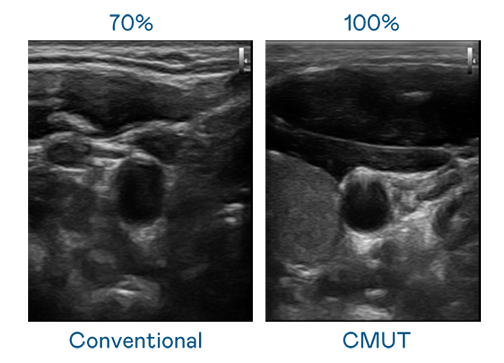

CMUT 技术是一种用电容式微机电元件来产生超音波讯号的技术。与传统 PZT 压电式技术相比,CMUT 频宽增加 30%,更宽频的超音波讯号让影像解析度大幅提升,是实现高影像品质医疗超音波扫描、促进精准医疗发展的关键技术。

大频宽带来超清晰影像

超音波影像的解析度高低,首先取决于探头能发出的讯号频宽。EZPay CMUT 可提供高清晰的超音波讯号,提供高频宽、高灵敏度、影像纹理细节更高的超音波影像,协助医护人员缩短影像判读时间及利用精准的医疗影像进行诊断。